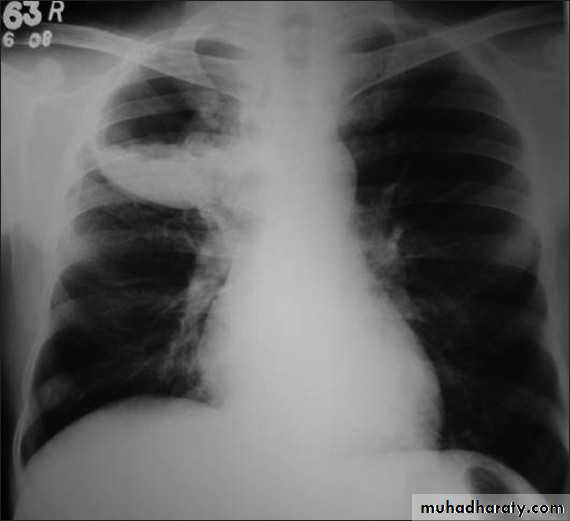

Right upper lobe collapse has distinctive features, and is usually easily identified on frontal chest radiographs .

Radiographic features

Chest radiograph

Collapse of the right upper lobe is usually relatively easy to identify on frontal radiographs. Features consist of :

increased density in the upper medial aspect of the right hemithorax

elevation of the horizontal fissure

loss of the normal right medial cardiomediastinal contour

elevation of the right hilum

hyperinflation of the right middle and lower lobe result in increased translucency of the mid and lower parts of the right lung

right juxtaphrenic peak

A common cause of lobar collapse is a hilar mass. When a right hilar mass is combined with collapse of the right upper lobe, the result is an S shape to elevated horizontal fissure. This is known as Golden S sign .

Non-specific signs indicating right sided atelectasis are also usually present including:

elevation of the hemidiaphragm

crowding of the right sided ribs

shift of the mediastinum and trachea to the right